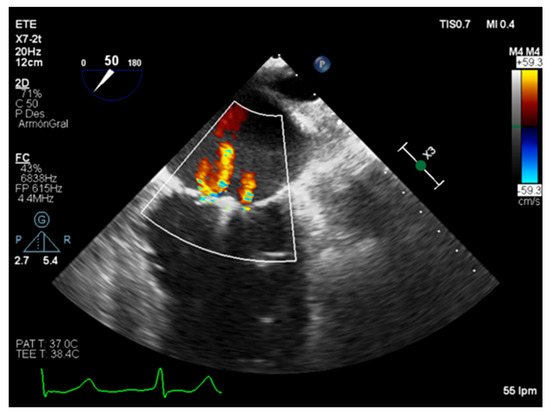

3.2. Semiquantitative and Qualitative Parameters